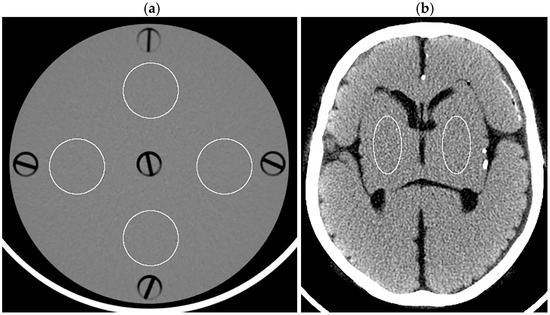

For 1.25 mm thick images, both observers judged DLR-M to be superior to HIR-L and HIR-H in all patients (p < 0.01; Table 4, Figure 6). For 0.625 mm thick images, one observer judged DLR-M to be significantly superior to HIR-L and HIR-H (p < 0.05 for both). The other observer judged DLR-M to be significantly superior to HIR-L (p < 0.05); however, the superiority of DLR-M over HIR-H was not statistically significant. For 5 mm thick images, both observers’ judgments were similar between DLR-M and HIR-L, indicating selecting HIR-L allows HIR to provide image quality comparable to DLR-M. For 2.5 mm thick images, one observer tended to judge DLR-M as superior to HIR; however, the difference between DLR-M and HIR-H was not statistically significant. The other observers’ judgment was almost identical between DLR-M and HIR-L. Overall, significant differences were not indicated between DLR-M and HIR for 2.5 mm thick images.

Figure 6.

Brain CT images of 1.25 mm thickness ((a) DLR-M; (b) HIR-L; (c) HIR-H) and 5 mm thickness ((d) DLR-M; (e) HIR-L; (f) HIR-H) in a 38-year-old male patient.